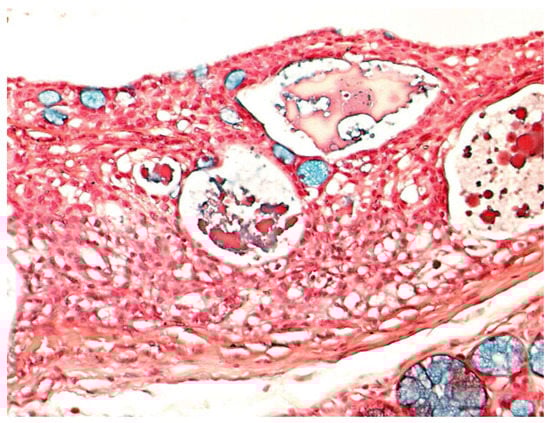

Gross examination disclosed well defined cystic lesions, and microscopically, at scanning magnification, a single cystic space was detectable in all samples, showing parietal proliferation of clusters of epithelial cells with a focal cribriform growth pattern (Figure 2). The central part of the cyst was filled with proteinaceous material and cholesterol crystals, while a distinct and complete rim of collagenous stroma separated the cyst from the surface epithelium and from adjacent lobules of mucous salivary glands. The clusters of epithelial proliferation (Figure 3) were composed by small columnar and intermediate cells, cells with prominent cytoplasmic clearing and marginated nuclei, scattered flat to polygonal cells showing epidermoid differentiation and a reduced number of large mucous-producing cells with multivacuolated cytoplasm. The latter were better highlighted with Alcian Blue (Figure 4) and Mucicarmine stains and also showed PAS-positivity, which was partly abolished after diastase treatment. Occasionally, smaller cystic spaces with cribriform appearance were evident within the neoplastic epithelial clusters, which were lined by cuboidal to columnar cells. Nuclear pleomorphism was minimal, as was mitotic activity (<1/10 high power fields), while inflammatory infiltration, necrosis and perineural invasion were undetectable; additionally, tumor-free margins (> 1 mm) were assessed in all cases. Patients had been followed-up for a minimum of five years (range: 62–120 mo.; median: 68 mo.) and had remained without evidence of disease up to January 2019.

Figure 4. Epithelial cells with multi-vacuolated cytoplasms and marginated nuclei demonstrate consistent Alcian Blue positivity, indicating mucous production. (Alcian Blue, x20).